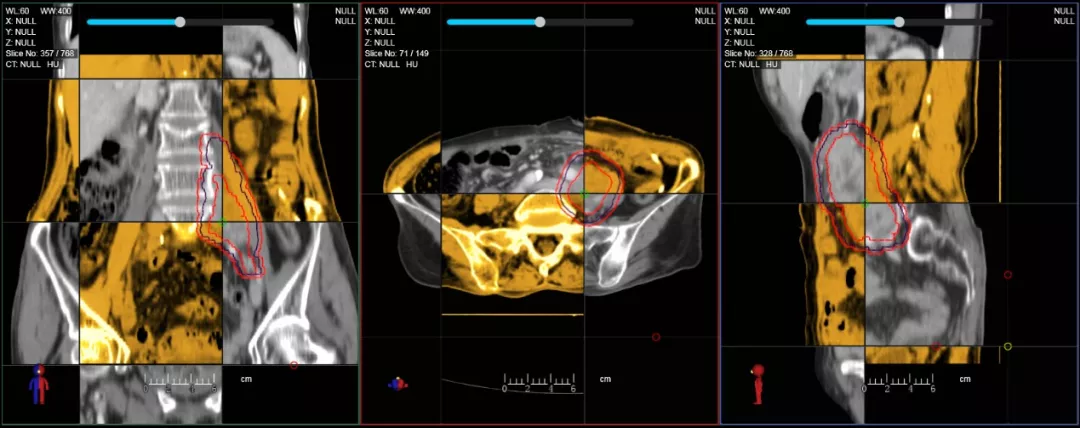

一體化CT-linac讓自適應放療ART概念變?yōu)楝F(xiàn)實?;颊呷煶虪顟B(tài)監(jiān)控,適時在線調(diào)整治療計劃,精準控制治療劑量,為患者動態(tài)定制個體化治療方案。uAI賦能智能勾畫和自動計劃,秒級勾勒靶區(qū)和危及器官,大幅縮短自適應放療時間。

在線自適應放療流程示意圖